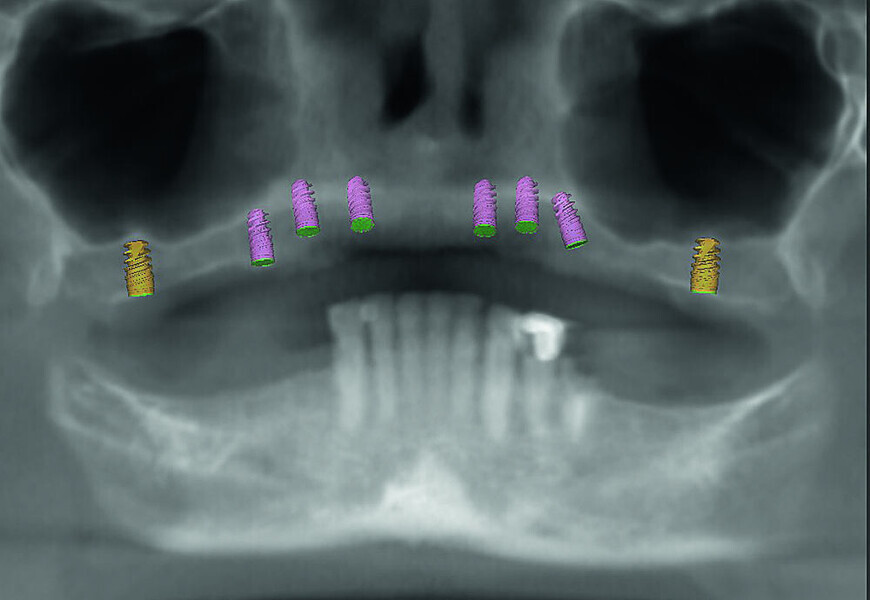

Fig 6 Analyse dento-faciale du traitement implantaire proposé dans l’arcade mandibulaire